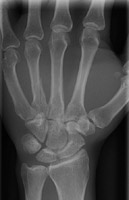

- Click on the image for a larger versionBPA radiograph of the hand. This details the appearance of an oblique fracture of the third metacarpal.